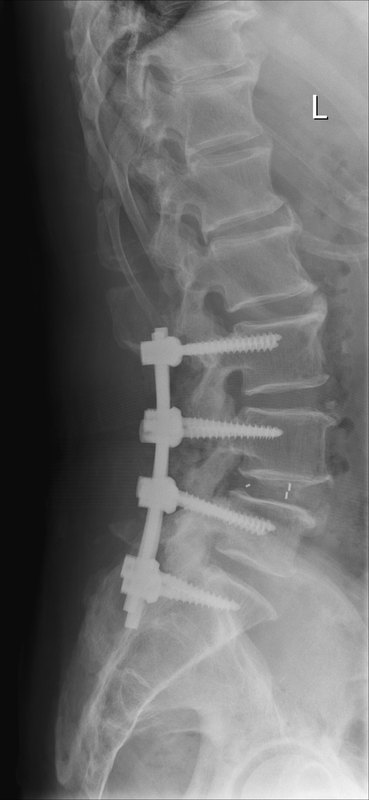

李大爺67歲,腰痛,腿痛有年頭了,現(xiàn)在走路100米左右就得休息休息,走不遠(yuǎn),越來(lái)越重。檢查了腰椎磁共振發(fā)現(xiàn)腰椎管狹窄明顯,腰椎失穩(wěn),間盤突出。 來(lái)醫(yī)院后,我們給做了椎管減壓,間盤切除,還有內(nèi)固定手術(shù)。術(shù)后第2天就開(kāi)始下床慢慢活動(dòng),疼痛感明顯改善,說(shuō)原來(lái)腰腿部就像纏捆著東西一樣,現(xiàn)在好多了。 腰腿痛,也可以找神經(jīng)外科來(lái)得到專業(yè)的診治。